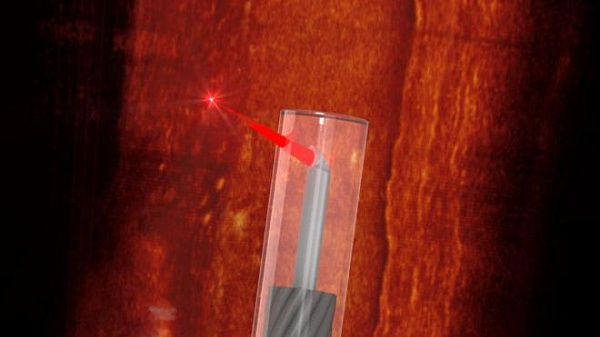

Международная команда исследователей разработала самый маленький в мире эндоскоп, способный проникать в сосуды для построения трёхмерной карты кровеносной системы – об этом

Представленное на этой неделе устройство получило диаметр меньше 0.5 миллиметра, причём в этот размер вошла и особая защитная оболочка. В состав эндоскопа также вошла напечатанная на 3D-принтере линза с боковым диаметром менее 0.13 миллиметров.

В качестве цели использования аппарата учёные назвали сканирование кровеносных сосудов на предмет жировых отложений и представление маршрута эндоскопа в виде 3D-карты.

Исследователи успешно протестировали устройство в кровеносных сосудах мышей и человека, и, по их словам, полученное с помощью эндоскопа изображение оказалось в пять раз лучше, чем у любого из существующих сегодня аналогов.

Фото: University of Adelaide